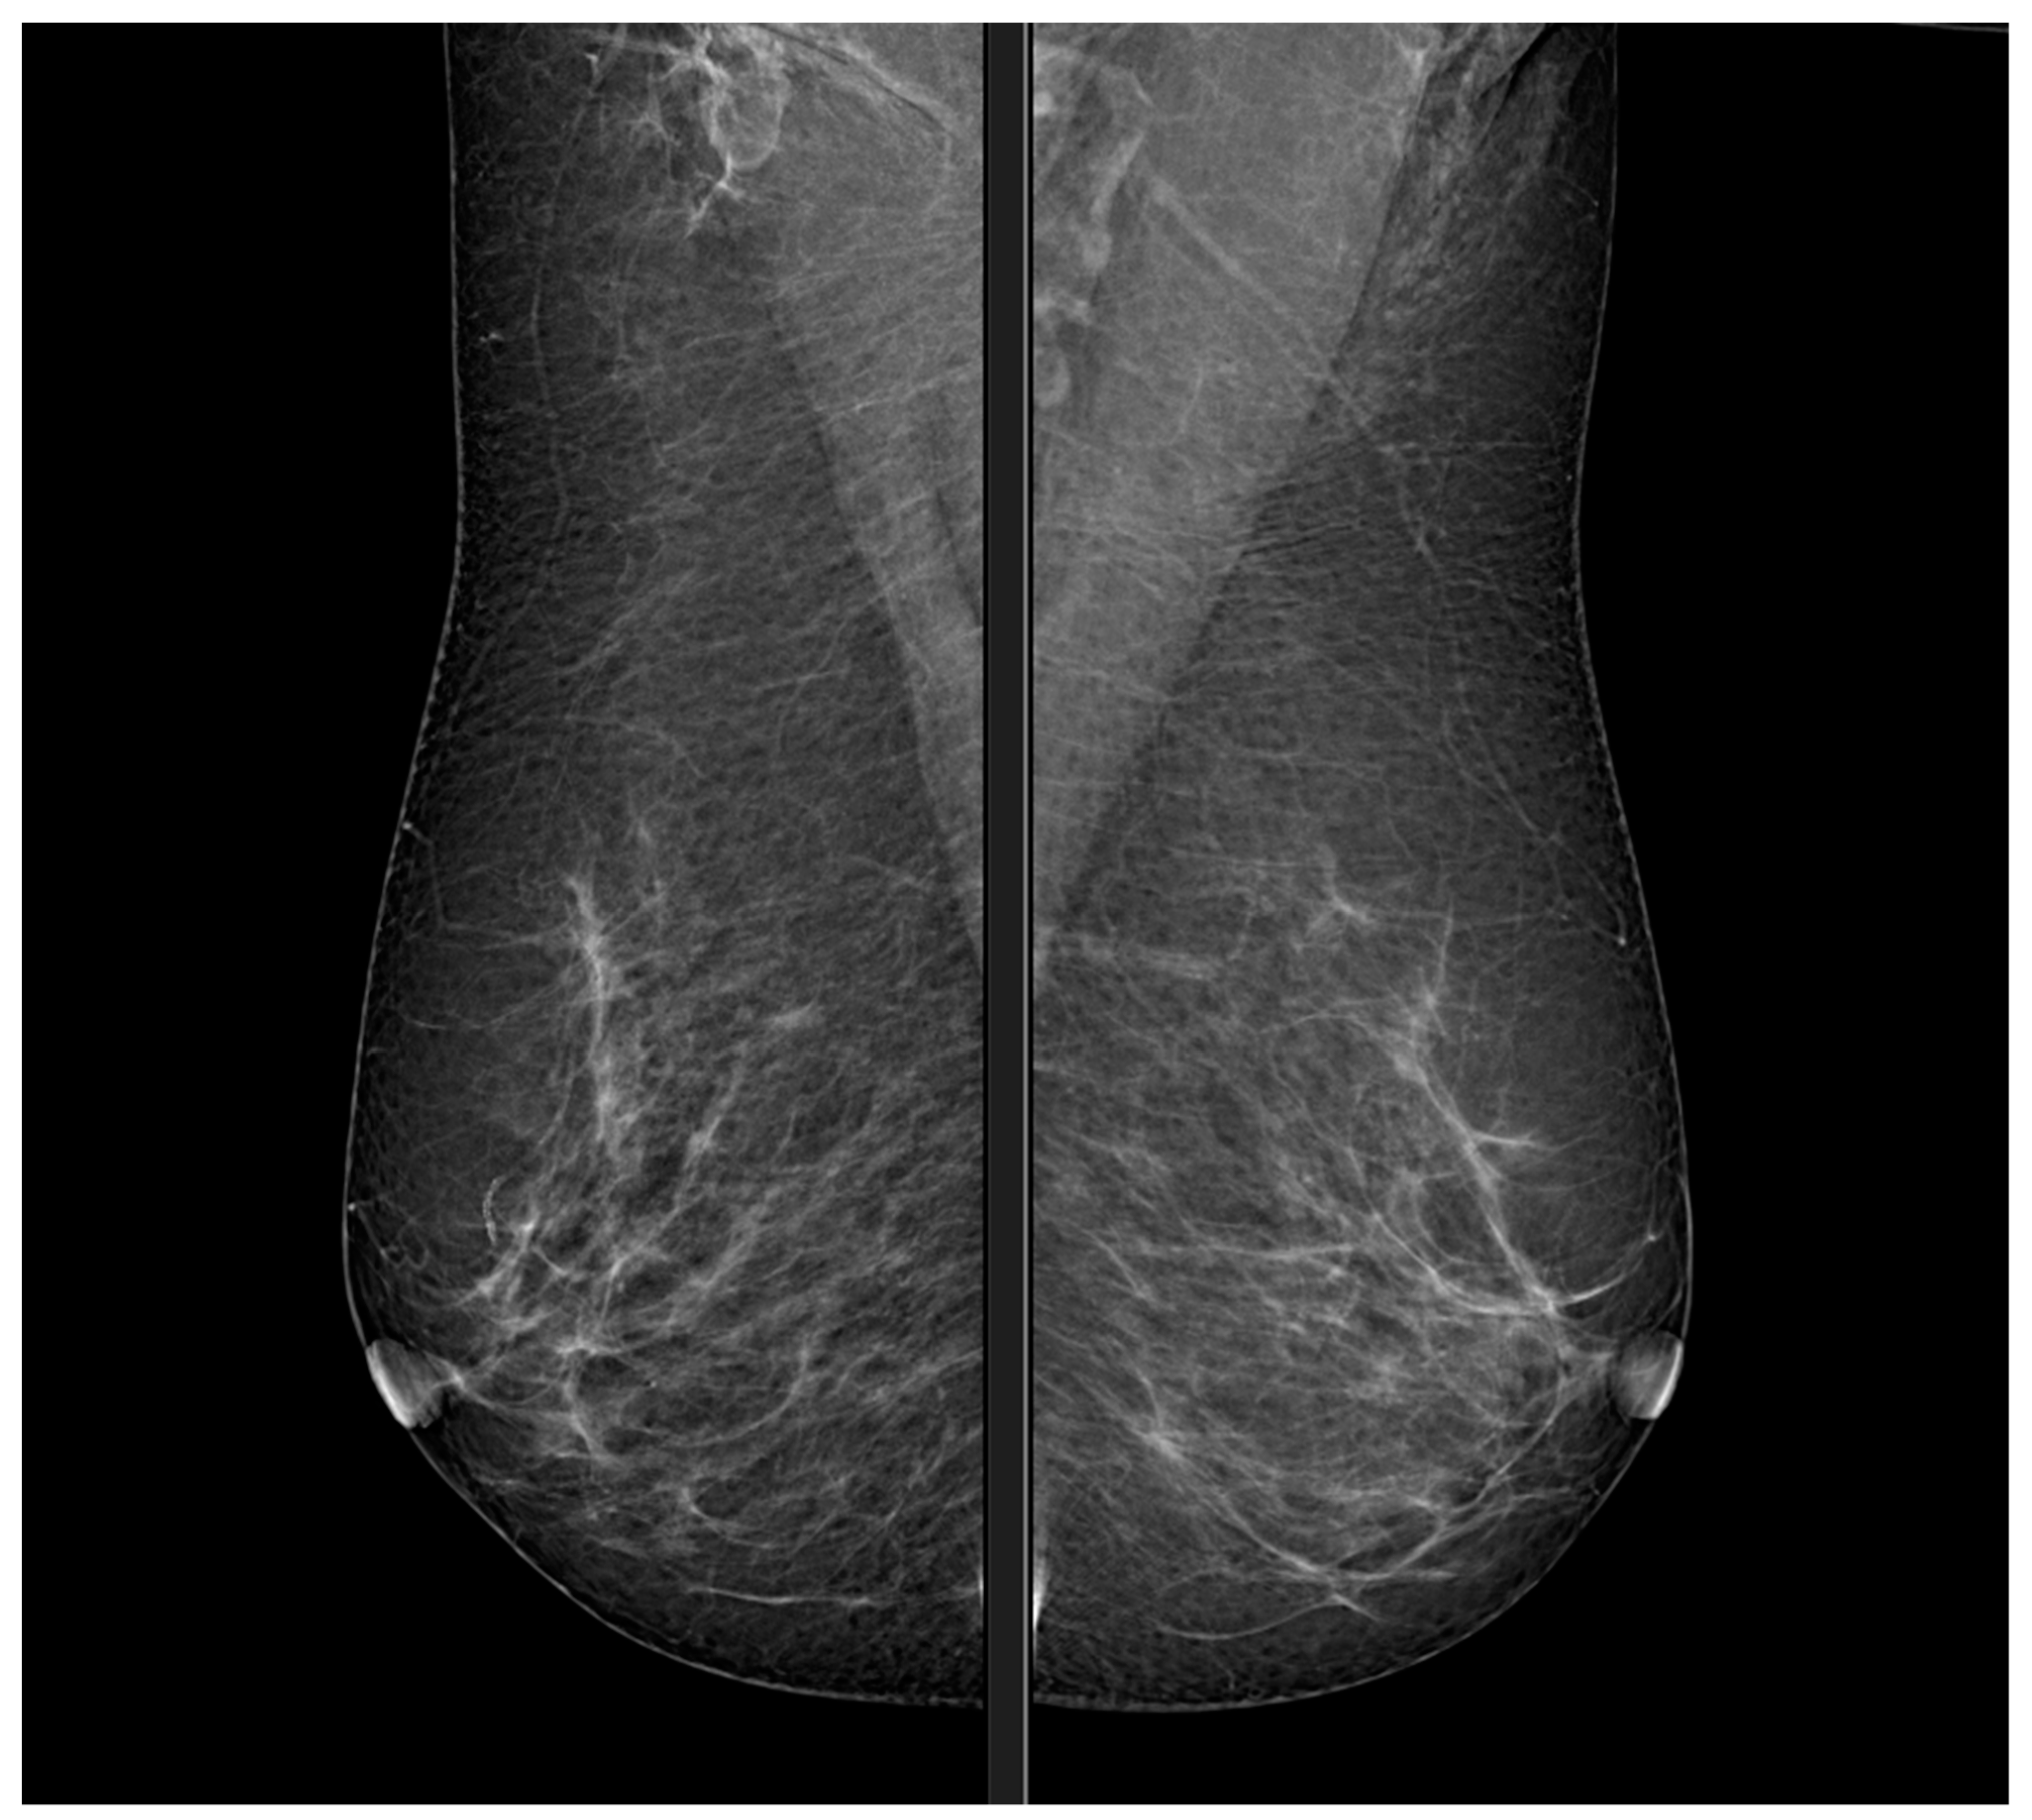

Xray Digital Mammogram or Mammography of Both Side Breast Standard Highline Mammography Find out about mammography and other. learn about the technique, performance, and interpretation of mammography and ultrasound for early. highline medical center imaging. after the advent of screening mammography, the proportion of detected breast tumors that were. la mammographie est une radiographie du sein qui permet de détecter les lésions cancéreuses et les tumeurs. when. Highline Mammography.

Xray Digital Mammogram or Mammography of Both Side Breast Standard Highline Mammography when performed in time, breast cancer screening allows better care of the disease. la mammographie est une radiographie du sein qui permet de détecter les lésions cancéreuses et les tumeurs. learn about the technique, performance, and interpretation of mammography and ultrasound for early. after the advent of screening mammography, the proportion of detected breast tumors that. Highline Mammography.